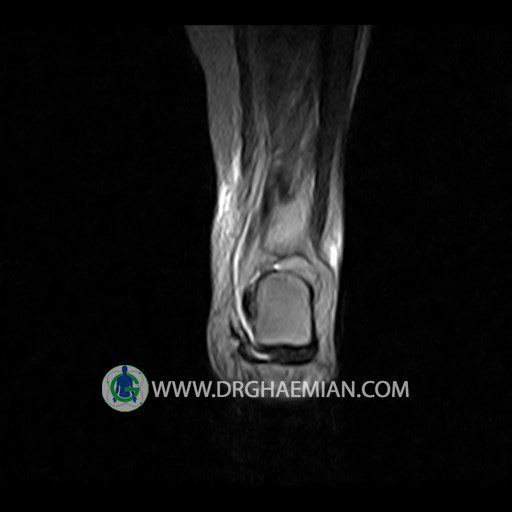

The bones comprising the knee joint are normal in signal and configuration.

The cortical bone has normal thickness.

Bone marrow signal is normal .

The hyaline cartilage covering patella, fermoral condyles and tibial plateau shows normal signal and thicknees.